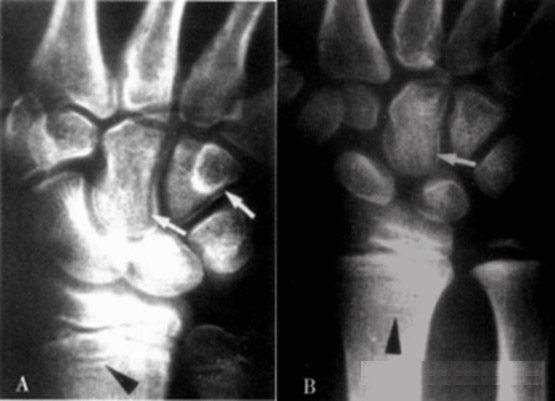

踝关节骺软骨x线图

6岁,骨骺已部分融合,患儿男童,12岁10个月,目前身高148cm,约两年前